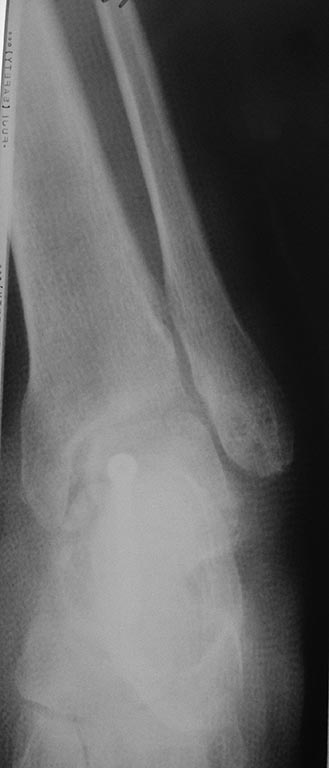

Два дня был без доступа к интернету. Во вложении недавний случай остеосинтеза оскольчатого переломовывиха таранной кости. Методика классическая. С анатомической репозицией и стабильной фиксацией. Без гипса после операции.